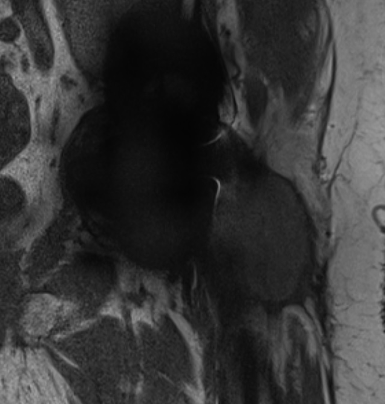

Adverse Local Tissue Reactions (ALTR)

Mechanism

Generation of biologically active, nanometer sized metal particles

- cause large inflammatory reaction

- pseudotumour (AKA aseptic lymphocyte-dominant vasculitis associated lesion ALVAL)

- can cause extensive soft tissue and bone loss

Diagnosis

Pain

High serum ion levels

Loosening on xray

Pseudotumour on MRI